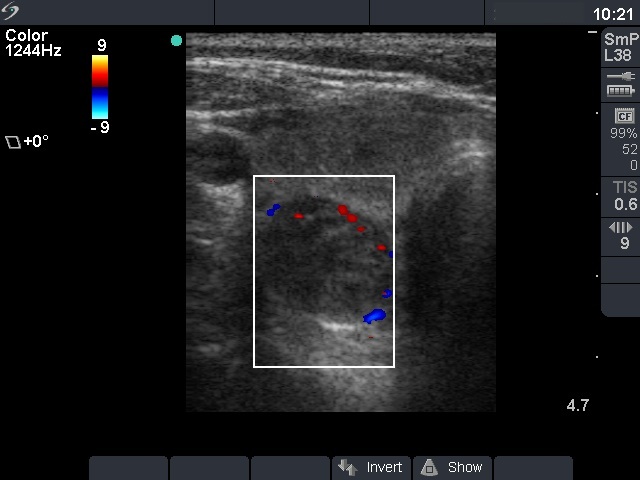

First examination (1st and 2nd rows of images)

Ultrasonography: the right thyroid contained three nodules, the two ventral lesions were minimally-moderately hypoechogenic, while the dorsal one was hypoechogenic. The latter presented a combined type 2 and type 3 vascular pattern.

Cytology was performed from the dorsal, hypoechogenic nodule and resulted in benign, follicular proliferation. The risk of a carcinoma was estimated to be less than 1%.